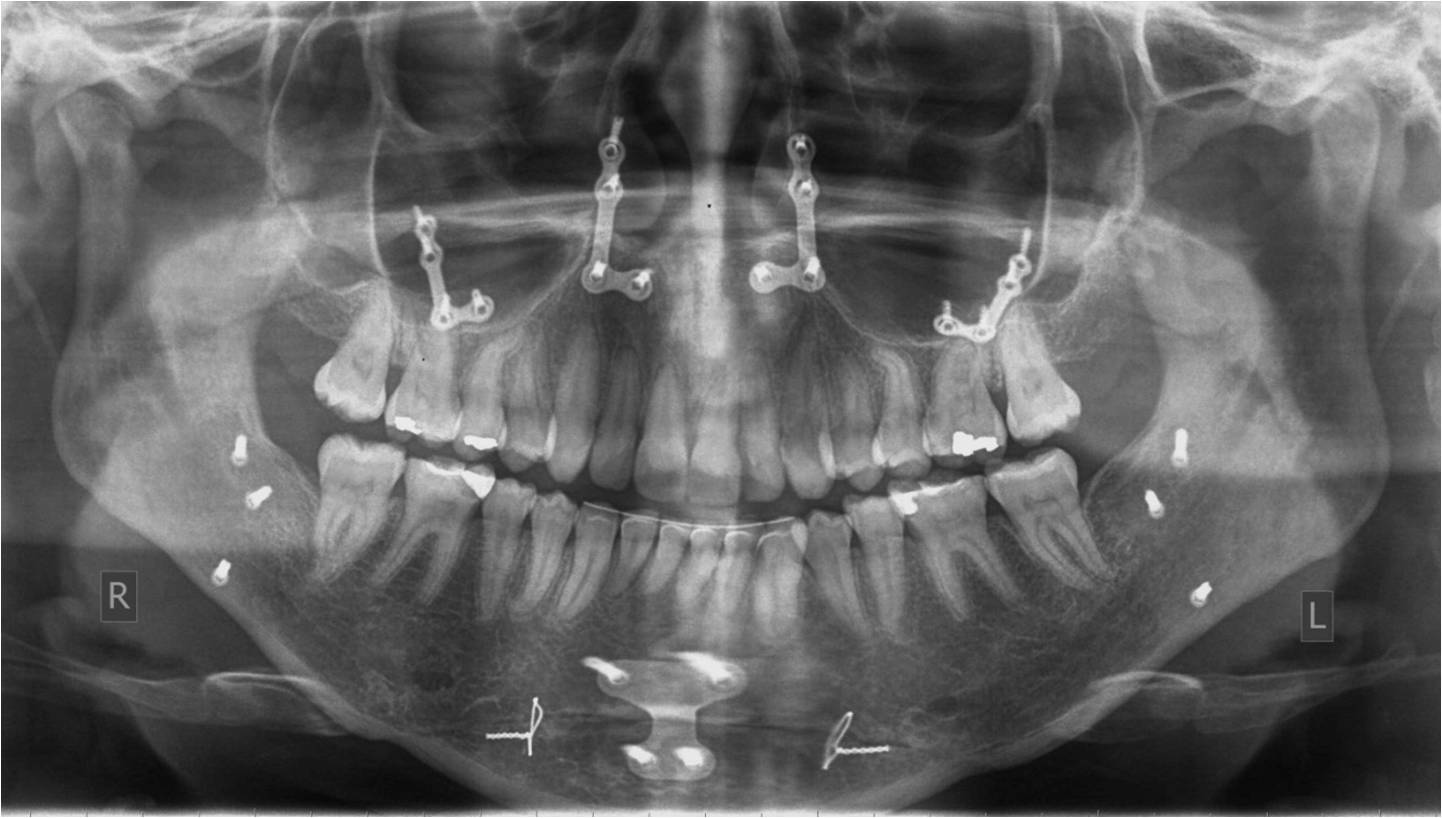

Η άμεσα προεγχειρητική προετοιμασία περιλαμβάνει τη λήψη φωτογραφιών της οδοντικής σύγκλεισης και του προσώπου, τη λήψη πανοραμικής και κεφαλομετρικών ακτινογραφιών, ενδεχομένως τη λήψη υπολογιστικών τομογραφιών των γνάθων, την κατασκευή γύψινων εκμαγείων μελέτης και την ανάρτηση αυτών με τη βοήθεια προσωπικού τόξου σε ημιπροσαρμοζόμενο αρθρωτήρα (Εικόνα 17), την εκτέλεση της επέμβασης κατά προσομοίωση πρώτα σε χαρτί (Εικόνα 18) ή εικονικά σε ηλεκτρονικό υπολογιστή (Εικόνα 19) και στη συνέχεια στα γύψινα εκμαγεία με σκοπό την κατασκευή χειρουργικών οδηγών (Εικόνα 20) που θα χρησιμοποιηθούν κατά τη διάρκεια της επέμβασης, για να υποδείξουν το είδος και το μέγεθος των μετακινήσεων των γνάθων με ακρίβεια χιλιοστού. Έτσι εξασφαλίζεται η ακριβής μεταφορά στο πρόσωπο του ασθενούς του συγκεκριμένου σχεδίου θεραπείας, στο οποίο έχουν καταλήξει σε συνεργασία ο γναθοπροσωπικός χειρουργός και ο ορθοδοντικός κατόπιν λεπτομερούς ανάλυσης, μελέτης και συζήτησης. Η σύγχρονη τάση, την οποία ακολουθεί και το ιατρείο μας, είναι όλη η προετοιμασία και προσομοίωση να γίνονται ψηφιακά και οι χειρουργικοί οδηγοί να εκτυπώνονται. Οι γνάθοι ακινητοποιούνται στις νέες τους θέσεις με πλάκες και βίδες οστεοσύνθεσης από τιτάνιο (Εικόνα 21). Αυτά τα υλικά δε χρειάζεται να αφαιρεθούν μετεγχειρητικά.